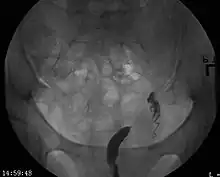

| A unicornuate uterus as seen on a hysterosalpingogram | |

A unicornuate uterus represents a uterine malformation where the uterus is formed from one only of the paired Müllerian ducts while the other Müllerian duct does not develop or only in a rudimentary fashion. The sometimes called hemi-uterus has a single horn linked to the ipsilateral fallopian tube that faces its ovary.[1]

Helpful techniques to investigate the uterine structure are transvaginal ultrasonography and sonohysterography, hysterosalpingography, MRI, and hysteroscopy. More recently 3-D ultrasonography has been advocated as an excellent non-invasive method to evaluate uterine malformations.[4]